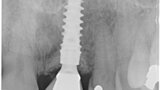

Fig. 33: Final result radiograph.